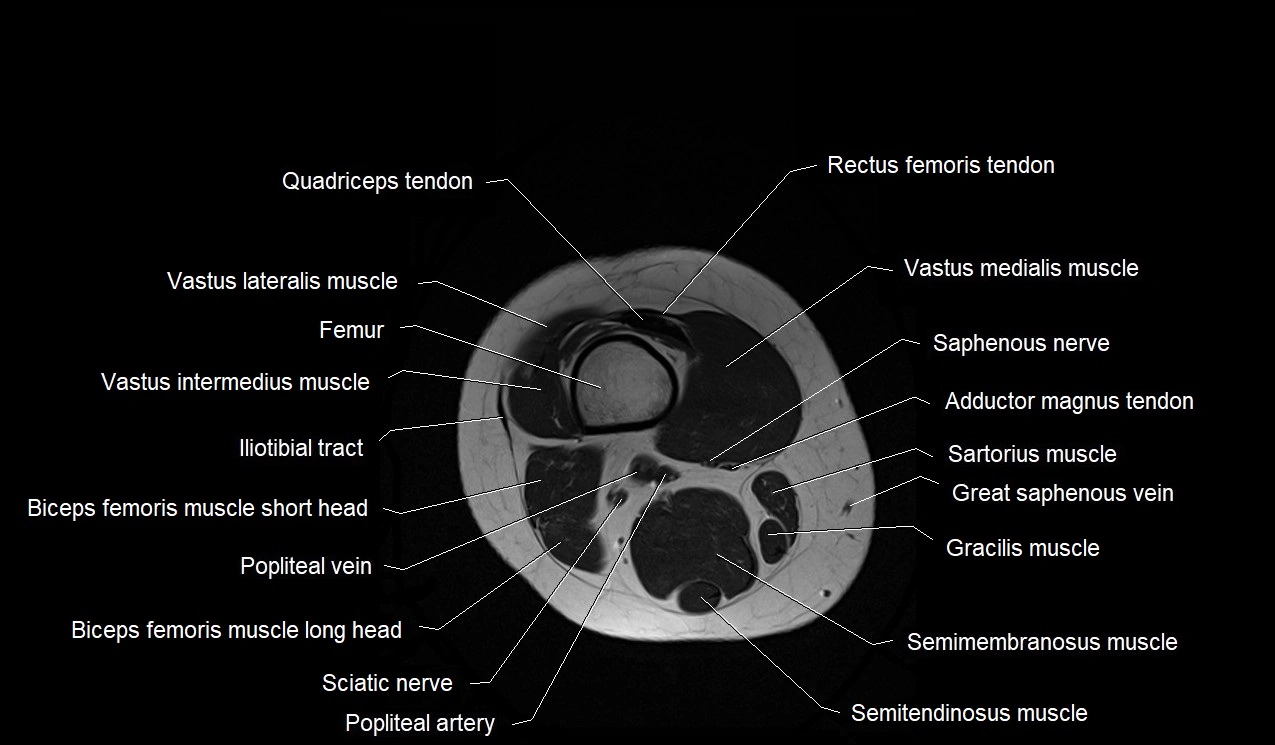

- Distal quadriceps femoris tendon

- Distal rectus femoris tendon

- Vastus lateralis muscle

- Femur

- Vastus intermedius muscle

- Iliotibial tract

- Biceps femoris muscle (Short head)

- Popliteal vein

- Biceps femoris muscle (Long head)

- Vastus medialis muscle

- Saphenous nerve

- Distal adductor magnus tendon

- Sartorius muscle

- great saphenous vein

- Gracilis muscle

- Semimembranosus muscle

- Semitendinosus muscle

- Tibial nerve

- Popliteal artery